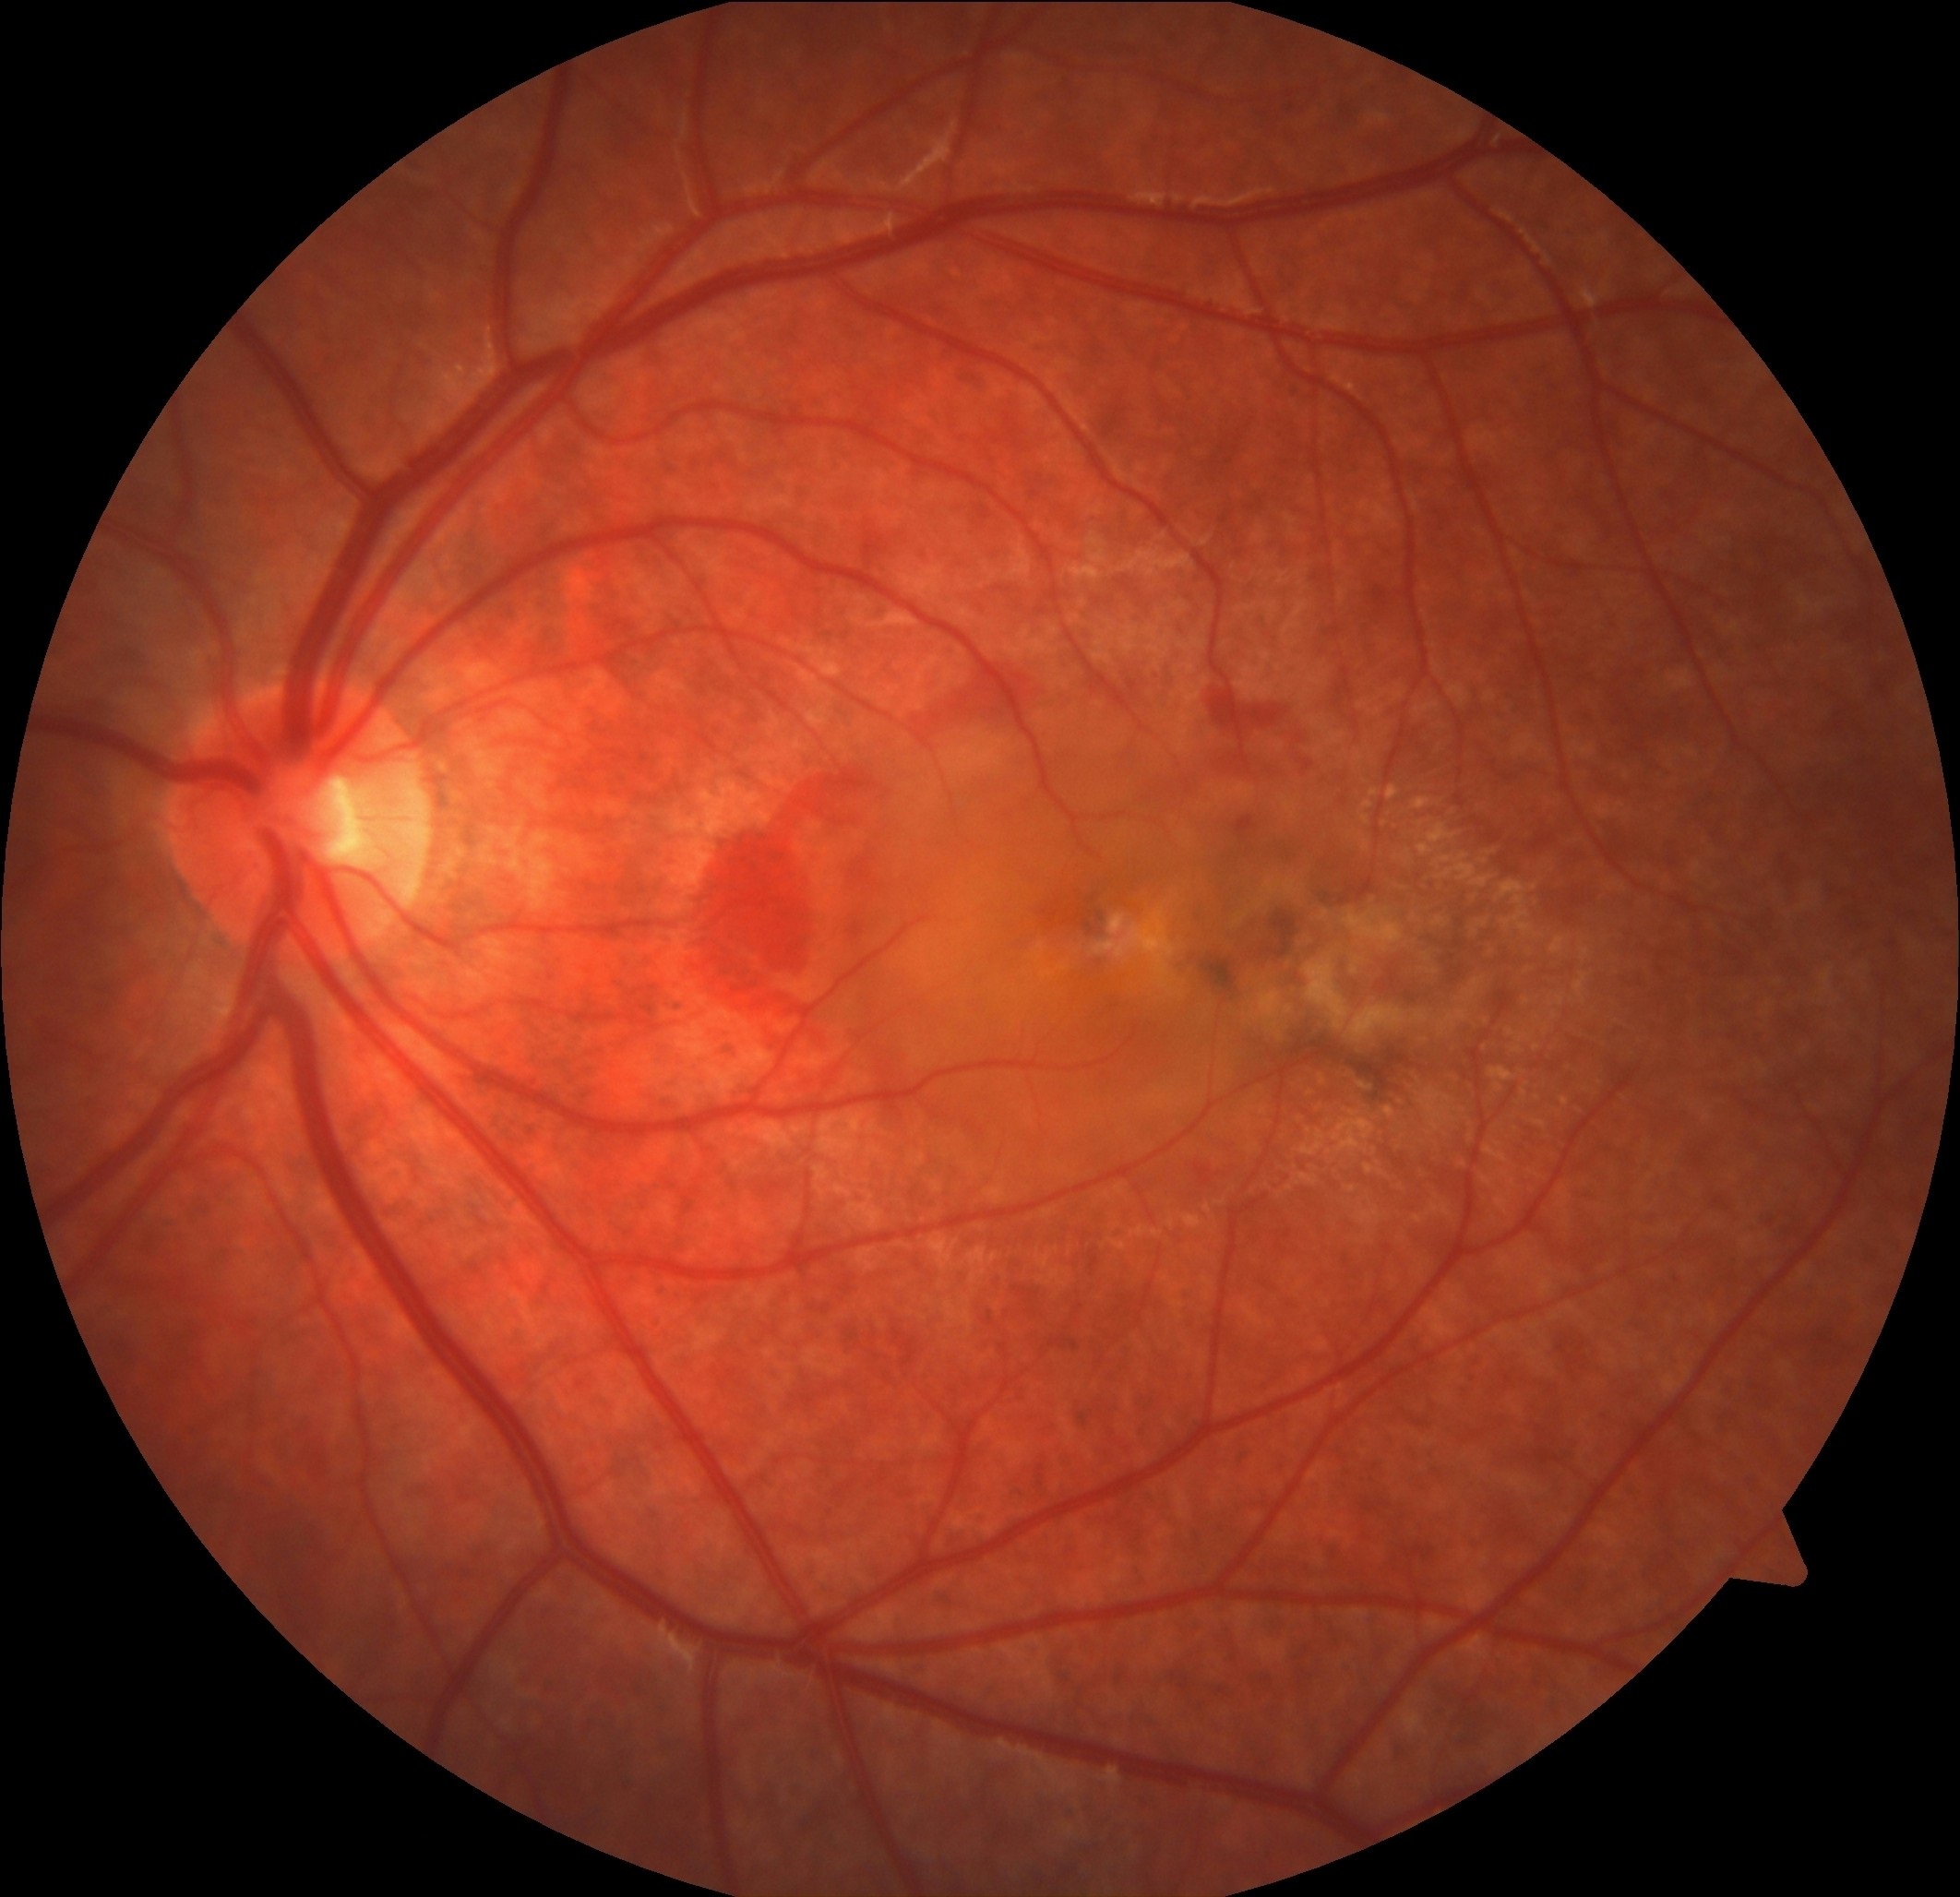

2026 Şubat Ayın Sorusu

Sağ gözde beş gündür artan görme azlığı olan 30 yaşındaki kadın hastanın renkli ...